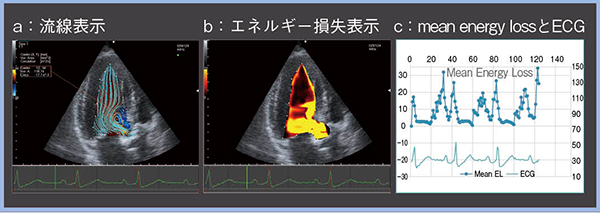

心臓の血流動態解析としては4D flow MRIなどがあるが,これを心エコーで実現したのがVFMである。VFMは,カラードプラ情報と心筋壁の運動情報から,流体の質量保存則に基づき超音波ビームと直交方向の速度成分を求め,血流速度ベクトルを表示する9)。VFMを用いて計測する指標の一つとしてエネルギー損失(energy loss)がある。隣り合う血流速度ベクトルの差が大きいほどエネルギー損失が大きくなり,左室内のエネルギー損失の大きさの違いによって心機能を詳しく評価できると考えられている。

図5,6は,重症の大動脈弁狭窄症の経カテーテル大動脈弁留置術(TAVI)前後のVFM画像である。VFMのエネルギー損失表示では,損失の程度が大きいほど濃い色で表現されるが,TAVI後の画像は色がやや薄く,数値的にも明らかにエネルギー損失が減少していた(図6 b,c)。TMFも確認したところ,TAVI前後でほぼ変化は見られないことから,TMFで確認できない変化をVFMのエネルギー損失表示ではとらえていると考えられる。

VFMは再現性良くエネルギー損失を評価可能であり,TAVI後のエネルギー損失の改善を確認できるなど,血行動態の変化および心筋の効率的な仕事量を鋭敏にとらえられる可能性がある。

図5 VFMで計測したTAVI前のエネルギー損失

図6 VFMで計測したTAVI後のエネルギー損失